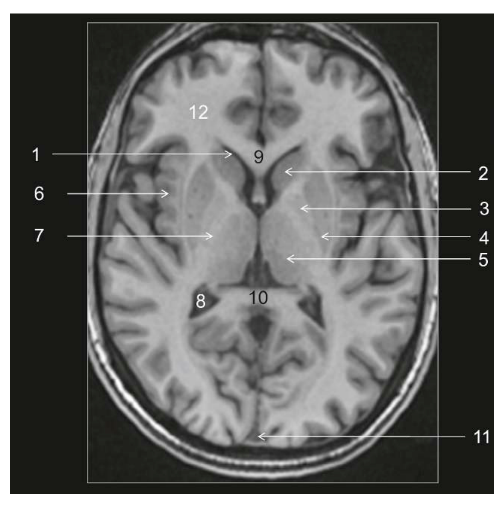

Coupe ?

Légende ?

Coupe ? Légende ?